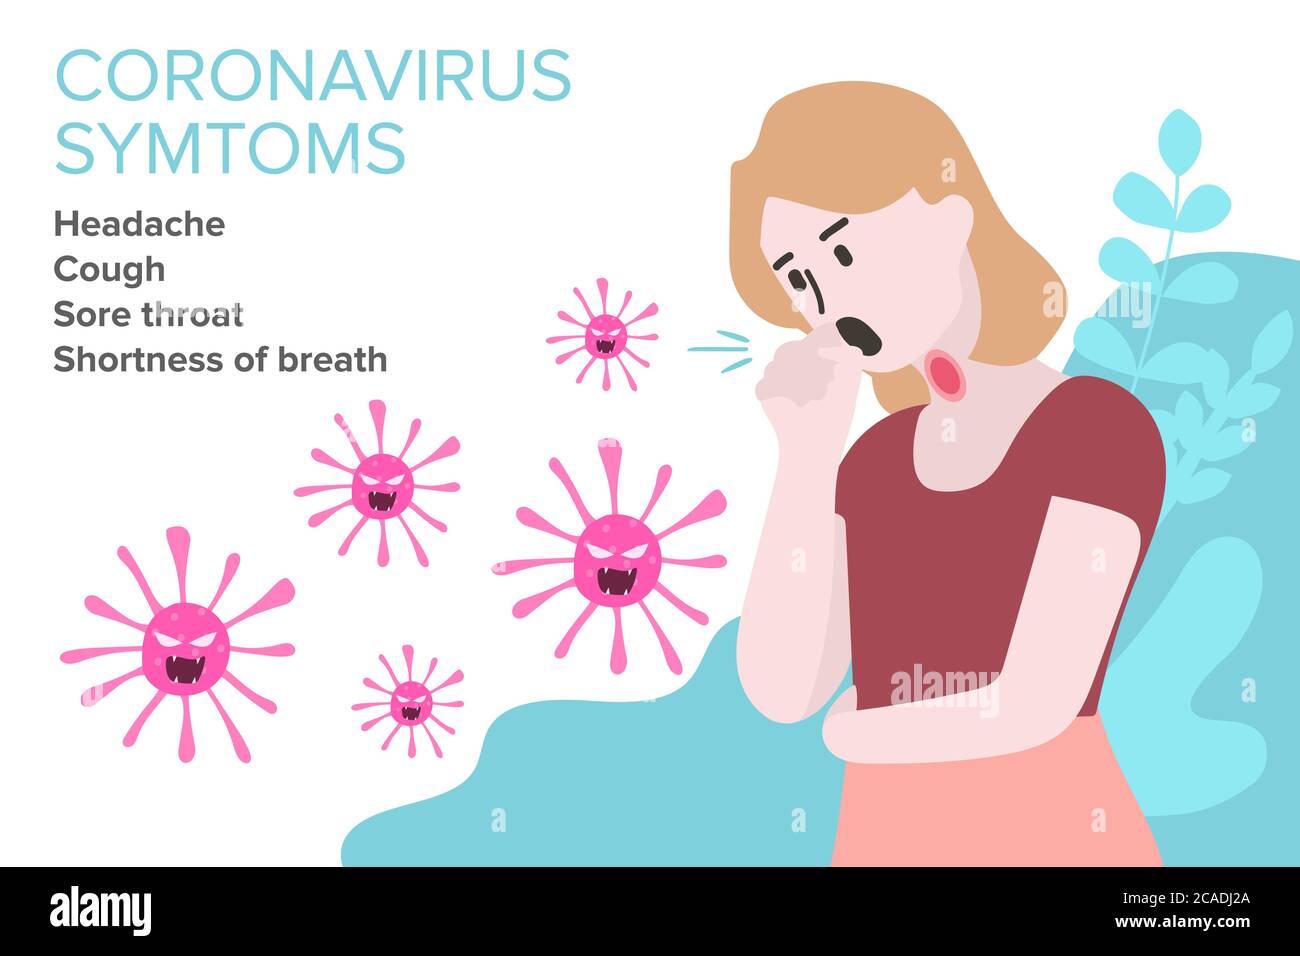

RF2CADJ2A–Segno infografica con Cartoon ha tosse, febbre, Gola irritata e freddo in Coronavirus o Covid-19 focolaio.